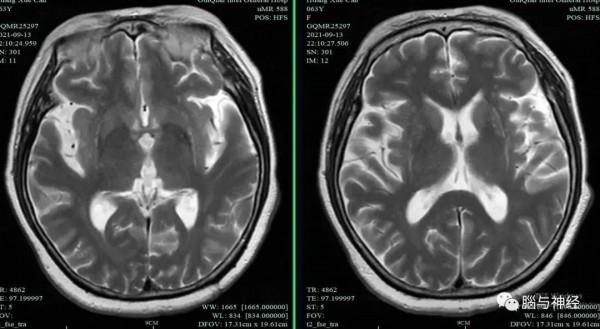

先看影像,可見殼核萎縮、外緣裂隙徵。

最典型還是SWI,類似尿毒症或糖尿病酸中毒的“叉徵”,可稱作“黑色叉徵”。殼核外緣的裂隙徵更明顯。

一是影像典型:殼核改變,包括殼核萎縮、殼核背外側低訊號、殼核外緣的裂隙徵都很有特點。不僅傳統的T2相,可以看出SWI、DWI和ADC圖對於殼核異常也很有診斷價值。請看文獻報道的DWI、ADC圖和SWI對MSA的診斷價值。